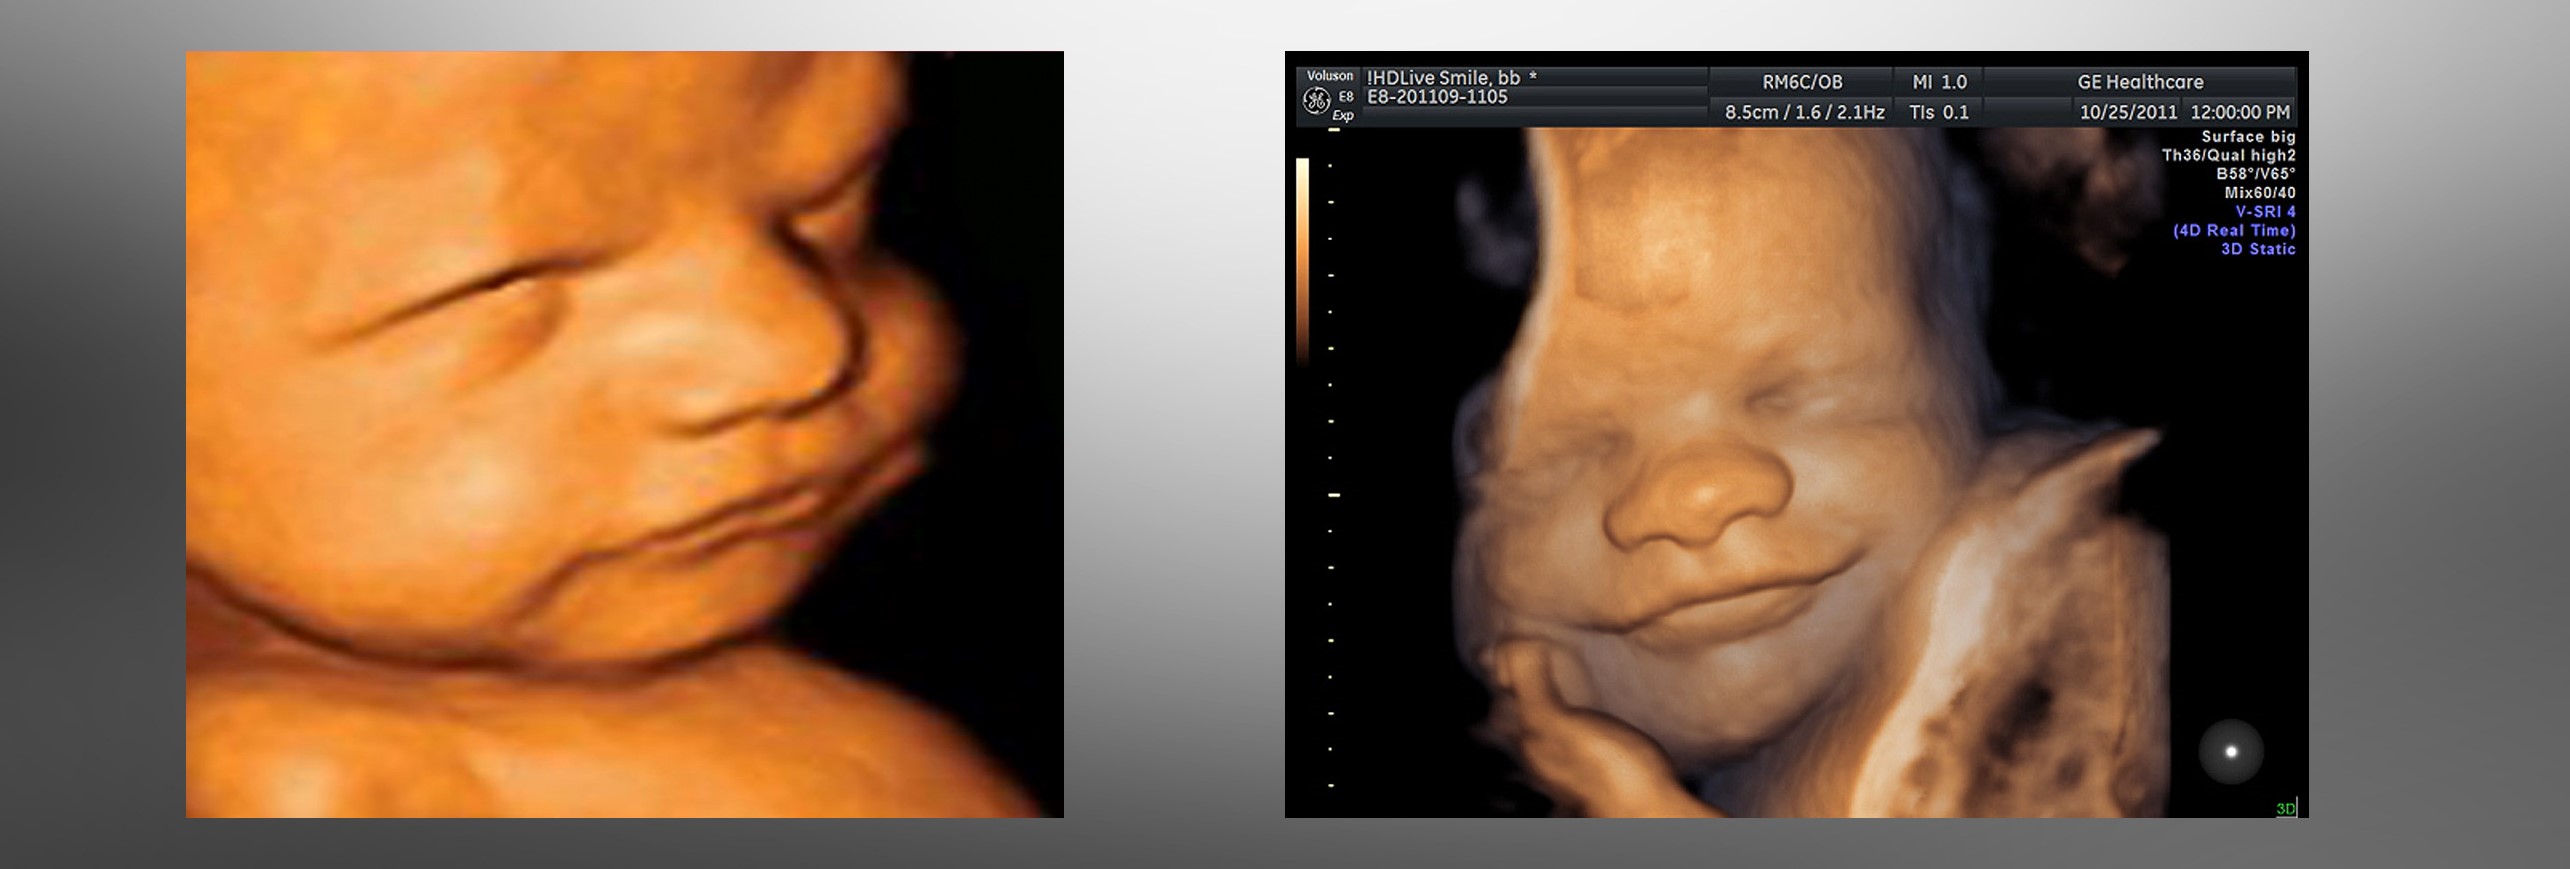

El vídeo de una ecografía en 4D se está viralizando en las redes sociales por mostrar escenas impresionantes de un bebé que, abrigado en el vientre de su madre, sonríe, se restriega sus ojitos, se estira, bosteza, mueve la boquita e incluso “dice adiós.”

La mujer, hasta entonces irreductible en la decisión de eliminar al niño, pudo ver, con toda riqueza de detalles, las imágenes encantadoras de un bebito que hacía prácticamente lo mismo que el bebé cuya ecografía compartimos. Y la ternura de ese pequeño ser lleno de vida le hizo llorar como antes nunca en su vida:

¡Pero el video de la ecografía que compartimos es muy real! ¡Lleno de vida en sus gestos frágiles y silenciosamente elocuentes, es una declaración silenciosa de humanidad!